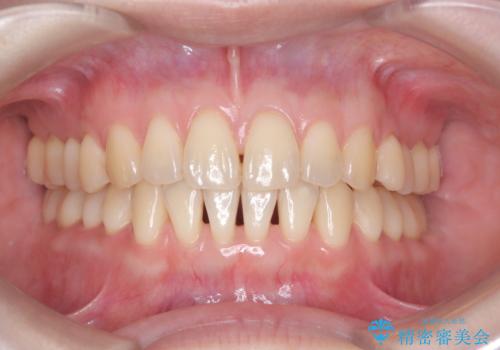

[ 前歯のねじれ・がたつき ] マウスピース矯正

![[ 前歯のねじれ・がたつき ] マウスピース矯正の症例 治療後](https://seimitsushinbi.jp/wp/wp-content/uploads/2024/02/e7a01485e4f4dd0da04705fde4cc34cc-500x350.jpg?v=1708502585)